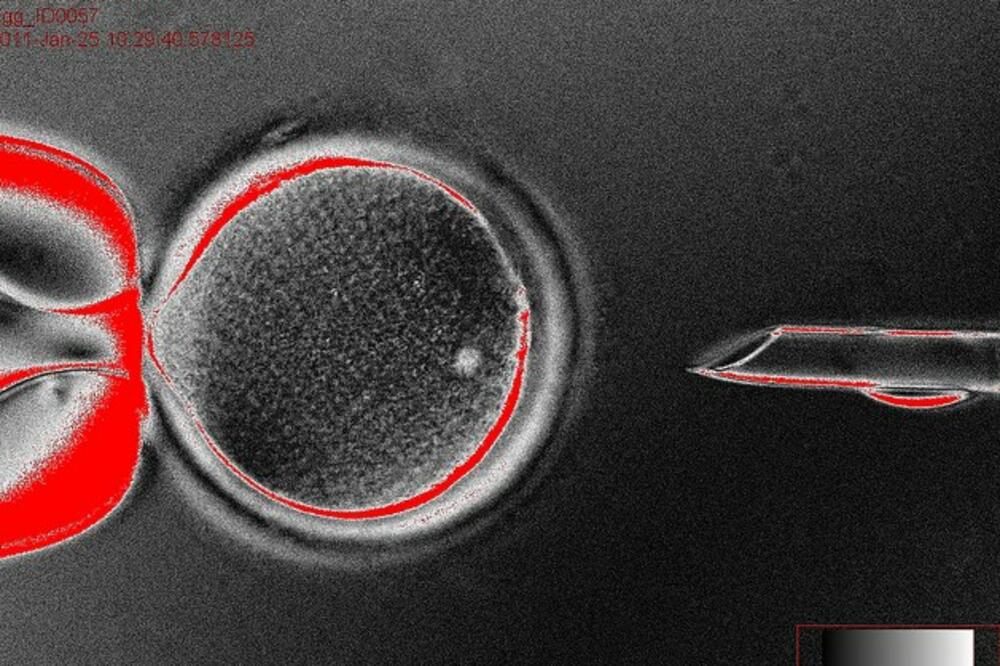

Matične ćelije, Foto: University of oregon